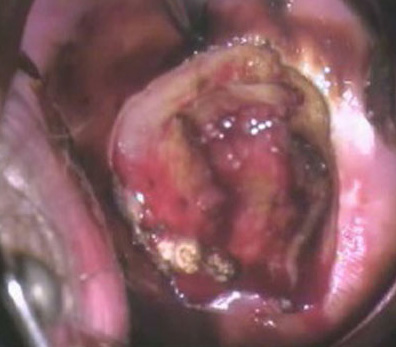

苔藓型外阴白斑

外阴白斑是由病变而引起的表皮增厚,表皮基底层色素脱失以及真皮浅层血管减少,致使外阴皮肤或粘膜色泽减退或呈白色。苔藓型外阴白斑有哪些症状,苔藓型外阴白斑可见于任何年龄,它的病理特征为表皮层过度角化甚至出现角栓,表皮萎缩变薄,黑色素细胞减少,胶原纤维结构丧失,真皮中层有淋巴细胞浸润。